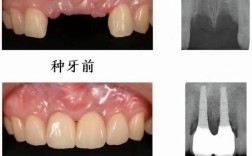

• 合肥种植牙价格大概多少?哪些因素会影响费用?

合肥种植牙价格大概多少?哪些因素会影响费用?

在合肥,种植牙的价格是一个大家非常关心的问题,但没有一个固定的统一价格,价格受多种因素影响,差异很大,以下是一个详细的说明,帮助你了解合肥种植牙的大致价格范围和影响因素:📍一、合肥种植牙大致价格范围(单颗)以下价格为市场常见的大致范围,...